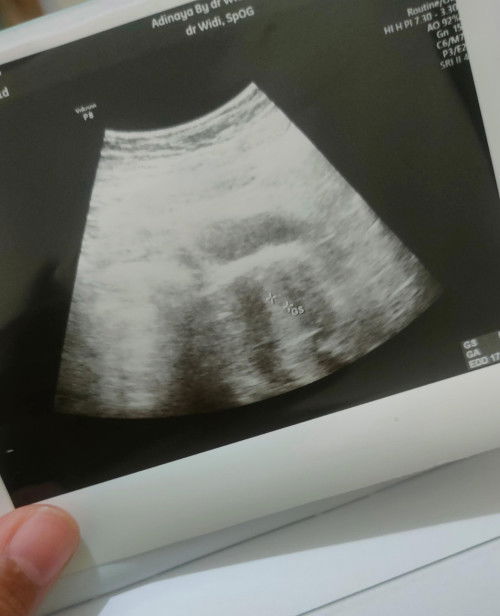

mauuuu tanya usg 5w

ini sudah ada kantung blm yaa

Saya lihatnya belum ada mom